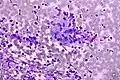

Granuloma. Field stain.